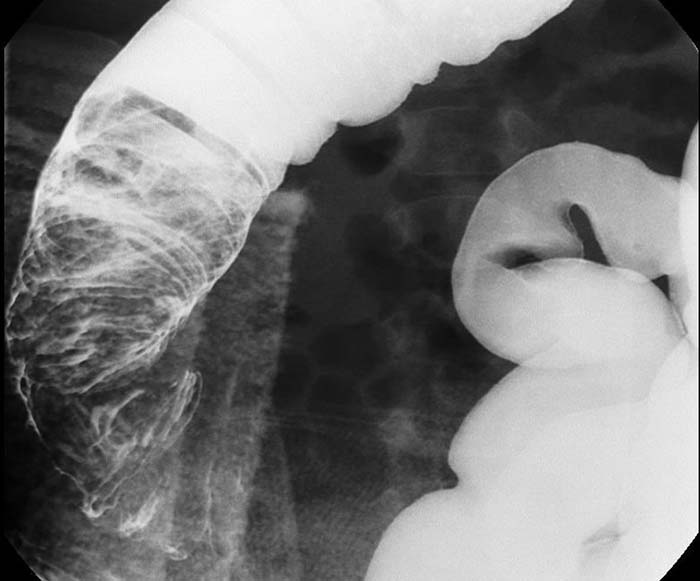

What is intussusception?

Telescoping of a proximal bowel segment into a distal segment, causing obstruction.

Bowel contents cannot pass through the telescoped segment.

Where does intussusception most commonly occur in children?

At the ileocecal valve.